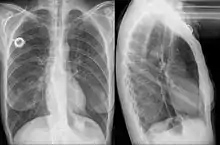

Additional images